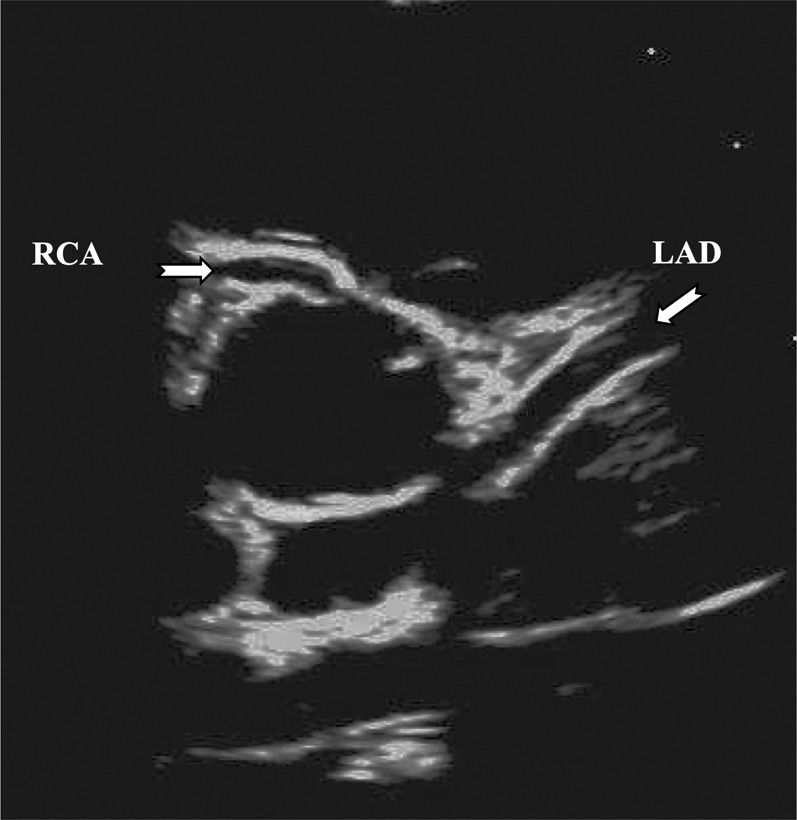

Table 2 shows conventional echocardiographic parameters, and Table 3 shows the results of coronary artery echocardiography. The coronary arteries from a typical MIS-C patient are depicted in Figure 1 . It is noteworthy that among 28 MIS-C patients, only 1 case (4%) manifested coronary artery abnormality in our cohort (coronary ectasia; z score: 3.15 in the right coronary artery). No segmental aneurysms were detected. On the other hand, in classic KD, 4 cases (20%) of coronary abnormalities including 2 with aneurysms (max z score: 5.0 in right coronary artery) were detected. During the early follow-up studies, the single MIS-C patient with coronary ectasia showed resolution of the ectasia (z score changed from 3.15 to 1.8 in right coronary artery), and no other progressive coronary lesions were detected in the MIS-C group.

Figure 1.

Echocardiographic Image of a Patient With MIS-C With Normal Coronary Arteries

Although the coronary artery may appear prominent, the Z score is 1.7 for left anterior descending artery (LAD) and 1.3 for right coronary artery (RCA).